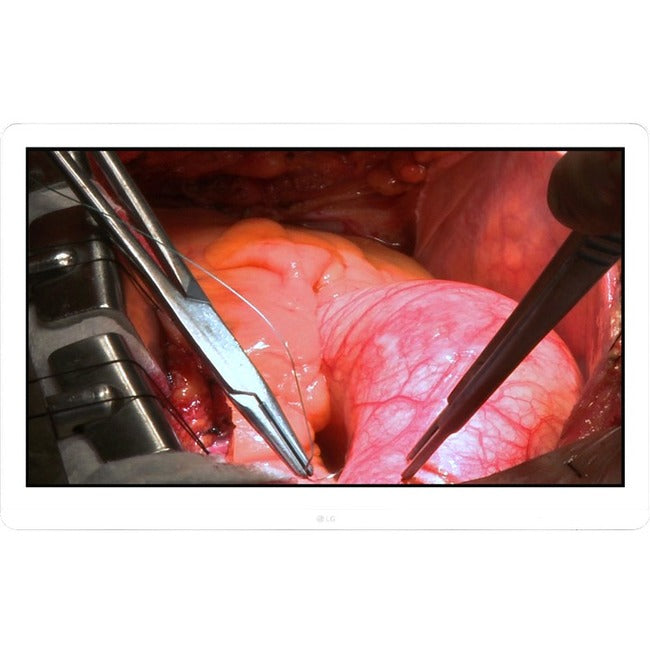

LG

SKU: 27HJ713S-W

LG 27HJ713S-W 27" 4K UHD LCD Monitor - 16:9 - White 27HJ713S-W

Sale price$4,898.99

Regular price$5,347.86